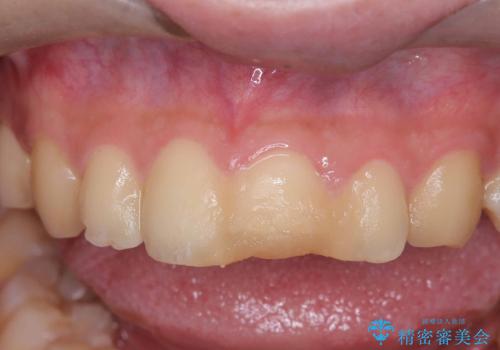

神経の状態が良好に保たれていることを確認した後、オールセラミッククラウンによる審美修復を行いました。

なお、最終補綴前にはオフィスホワイトニングを実施し、より自然で明るい仕上がりを得ることができました。